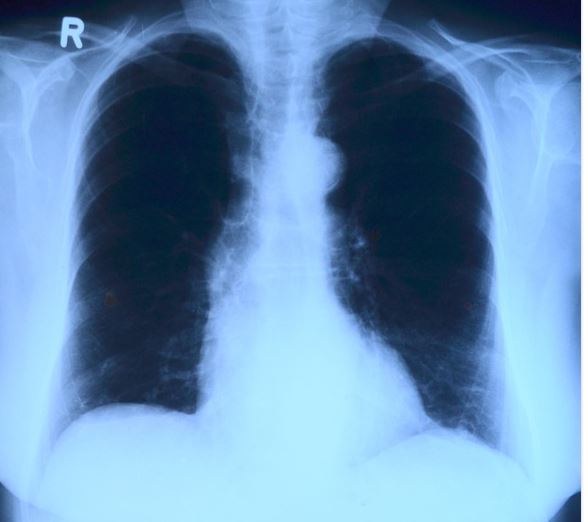

ARDS je závažný stav charakterizovaný jako respirační selhání, tj. selhávání plicních funkcí, které v mnohých případech i přes zákrok lékaře může skončit smrtí.